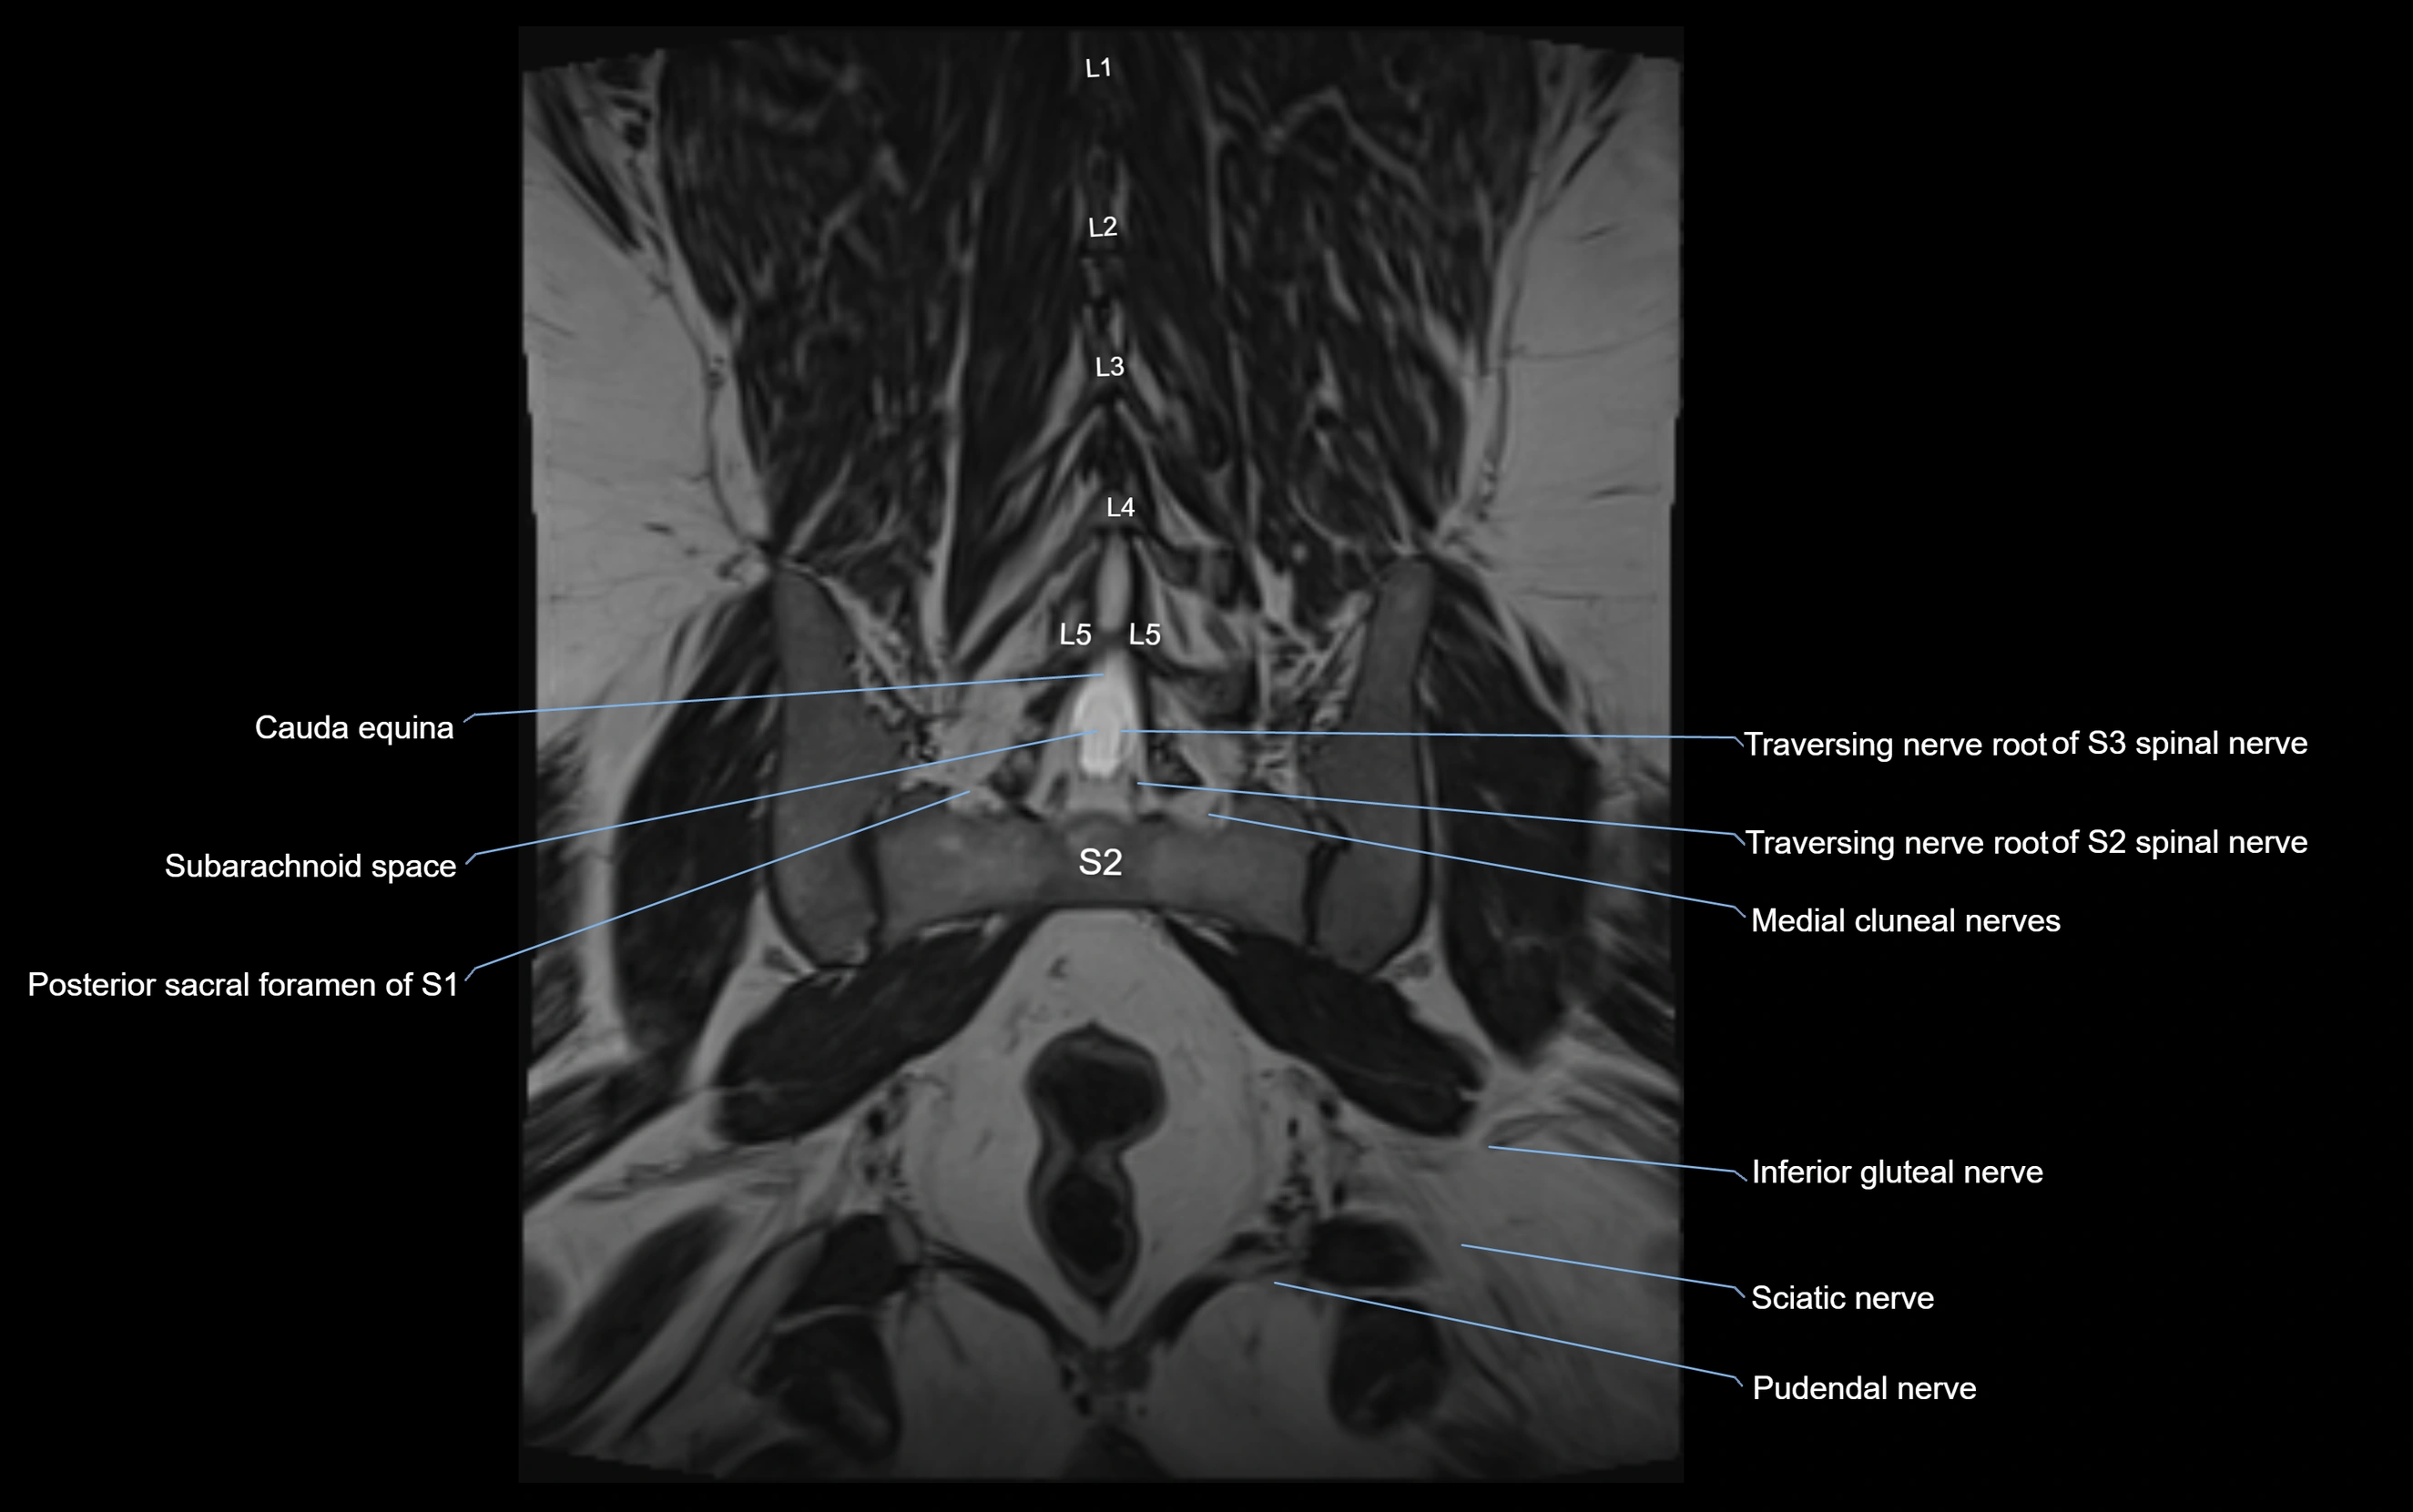

MRI Appearance

T1-weighted images:

• Nerve appears as a very thin low-to-intermediate signal intensity structure

• Surrounded by bright fat, aiding visualization

T2-weighted images:

• Nerve shows intermediate to mildly hyperintense signal compared to muscle

• Pathological involvement appears brighter

STIR (Short Tau Inversion Recovery):

• Normal nerve appears dark

• Inflamed or entrapped nerve appears bright hyperintense

T1 Fat-Sat Post-Contrast:

• Normal nerve enhances minimally

• Pathologic nerve (neuritis, entrapment, tumor infiltration) shows focal or diffuse enhancement

3D T2 SPACE / CISS:

• Nerve appears intermediate to mildly hyperintense compared to muscle

• Surrounded by bright fat or CSF, improving visualization

• Best sequence for mapping small pelvic nerves such as the anococcygeal